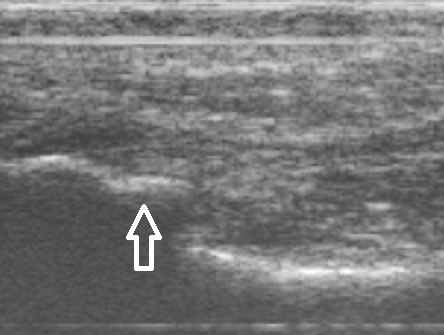

De podoloog Arnhem maakt een echo van uw voet om te kunnen zien of er sprake is van fasciitis plantaris of een hielspoor. Combinaties van beide klachten komen vaak voor.

Mortonse Neuralgie is door de podoloog goed te diagnosticeren. De neuroom ( zenuwverdikking) is soms duidelijk zichtbaar tijdens ons echo-onderzoek. Compressie van alle middenvoetsbeentjes, het knijpen in de voorvoet zal de klachten provoceren. Vaak horen we bij het knijpen in de voorvoet ook een klik (Mulder’s Kliktest). Deze klik wordt veroorzaakt door het verspringen van het neuroom tussen de middenvoetsbeentjes van de derde en vierde teen.